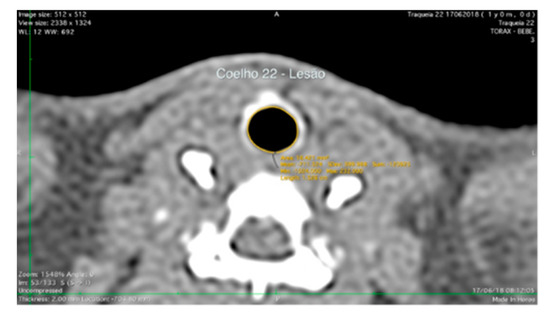

3.2. Computed Tomography Scanning Findings

| Tomography Analysis | |||||

|---|---|---|---|---|---|

| Global Mean | |||||

| Variable | Group | Value (mm2) | Min; Max; Median (mm2) | p Value | Test |

| Lesion Area | C {n = 10) | 18.71 | 11.37; 33.5; 13.1 | 0.211 | ANOVA-Oneway |

| AM {n = 10) | 14.15 | 11.2; 16.1; 14.3 | |||

| AM + hucMSCs {n = 10) | 25.44 | 14.7; 47.4; 18.4 | |||

| Area without Lesion | C {n = 10) | 25.10 | 19.1; 35; 24.2 | 0.811 | Kruskal-Wallis |

| AM {n = 10) | 23.87 | 22.5; 26.2; 23.4 | |||

| AM + hucMSCs {n = 10) | 26.96 | 18.9; 47.9; 19.8 | |||